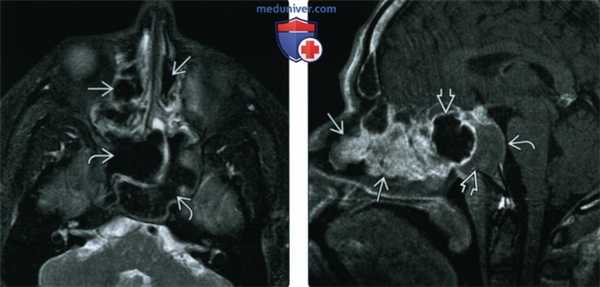

(Слева) При корональной «костной» КТ определяется снижение пневматизации левой верхнечелюстной пазухи, устье которой расширено. Визуализируется большой одиночный полип, пролабирующий через устье в полость носа и приводящий к обструкции среднего носового хода.

(Справа) При сагиттальной МРТ Т1 визуализируется крупный полип ва с промежуточным сигналом, пролабирующий из полости носа в носоглотку. Обратите внимание на нормальный гиперинтенсивный сигнал в небе ниже полипа. Ткань аденоидов слегка гиперинтенсивна по сравнению с полипом.

(Слева) При аксиальной «костной» КТ определяются типичные признаки АХП. Пневматизация правой верхнечелюстной пазухи снижена, визуализируется полиповидное мягкотканное образование, пролабирующее в полость носа. Сзади полип пролабирует через хоану в носоглотку.

(Справа) При аксиальной МРТ Т2 FS у ребенка определяется гиперинтенсивный АХП слева. Видны антральный и носоглоточный ва компоненты. АХП гиперинтенсивнен по сравнению с нижней носовой раковиной.

(Слева) При корональной МРТ STIR визуализируется типичный АХП, распространяющийся через устьев в полость носа. Внутриносовой компонент ва определяется изнутри от гипоинтенсивной нижней носовой раковины.

(Справа) При аксиальной МРТ Т1С+ FS визуализируется гантелеобразный назохоанальный полип, блокирующий хоанальные отверстия и заполняющий носоглотку. Вокруг образования определяется лишь периферическое контрастное усиление. Обратите внимание на ретенционные кисты, а верхнечелюстных пазухах.